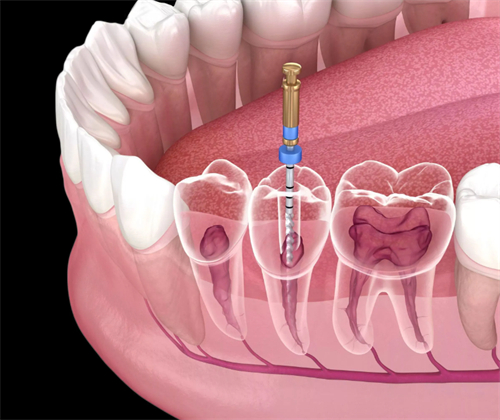

单颗牙根管治疗:约为1200元左右,另有说法为500元起,或880元起,或1000~1500元/颗

多根牙根管治疗:1500~2500元不等

打桩费用:额外收费,大约在500~1500元之间